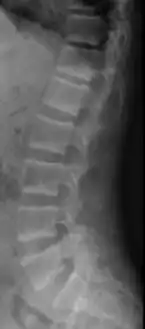

X-ray of a subtle "rugger jersey spine" due to sclerotic bands adjacent to the vertebral endplates.[17] -